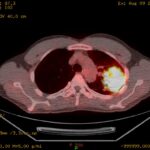

実は私自身、大きな病気を経験しています。 「しんどい」という言葉の重さを、身体で知っているから。

子どもの頃に小児喘息を経験し、40代では肺がんとも向き合いました。

だから「しんどい」という言葉を、理屈じゃなく、身体の奥で受け取ることができる。 そう思っています。

病気になってよかった、とは言えへん。 でもあの経験があるから、目の前の人のしんどさが、ちゃんと届く。

それが私の、唯一の強みかもしれない。

私自身、幼少期の喘息、40代での肺がんという経験を経て、今ここに立っています。だから、あなたの「しんどい」が本物だということ、ちゃんとわかります。